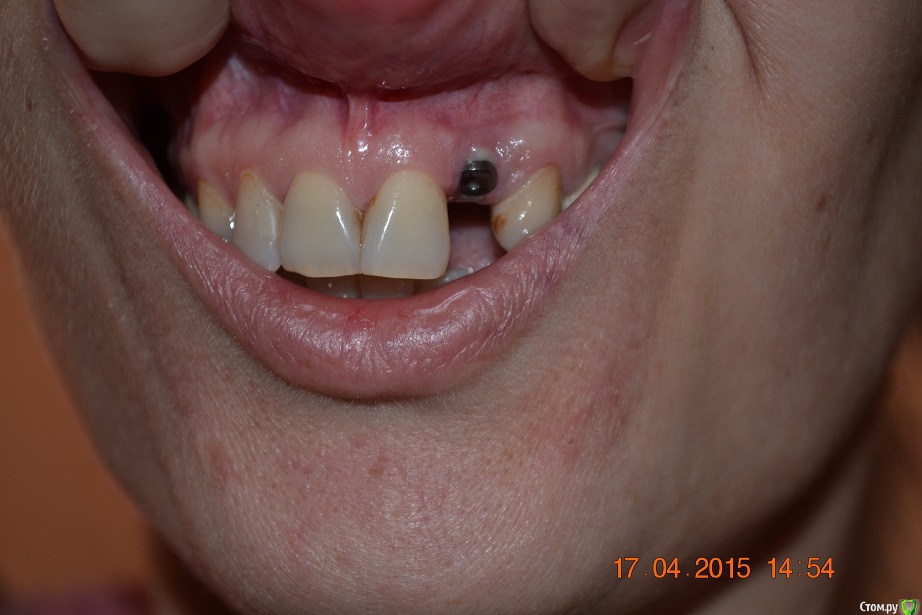

nat-man Опубликовано 17 апреля, 2015 Поделиться Опубликовано 17 апреля, 2015 (изменено) ЗДРАВСТВУЙТЕ, УВАЖАЕМЫЕ СПЕЦИАЛИСТЫ!Поставили формирователь 12 апреля , мне показалось, что стоит высоко, но сильно не беспокоилась,но после консультации с ортопедом 14 апреля расстроилась. Собираюсь ставить керамическую коронку, ортопед предложил верх коронки покрасить под цвет десны или искуственную десну с сосочками.... или к коронке прикреплены эти сосочки,,, вообщем полное фиаско моей мечты о зубе, который "растет" из десны и который, не отличить от настоящего... Ни фотографий, ни готовых коронок ортопед не показал, приходится пользоваться своей фантазией и интернетом. Честно говоря, я в шоке.... Хочу свою десну.... Почему возникла такая проблема с десной? Можно ли ее наростить? или может есть другие варианты? Изменено 17 апреля, 2015 пользователем nat-man Ссылка на комментарий

red_butler Опубликовано 17 апреля, 2015 Поделиться Опубликовано 17 апреля, 2015 спасибо, а кто проводит такие операции? сам хирург-имплантолог который ставил имплант? почему сложилась такая ситуация с десной? это моя вина или из-за слишком высокого уровня установки импланта? спасибо.делает хирург который это умеет, да имплант поставлен слегка выше. Покажите фото своей улыбки Ссылка на комментарий

nat-man Опубликовано 17 апреля, 2015 Автор Поделиться Опубликовано 17 апреля, 2015 вот как-то так Ссылка на комментарий

red_butler Опубликовано 17 апреля, 2015 Поделиться Опубликовано 17 апреля, 2015 требуется пластика десны Ссылка на комментарий